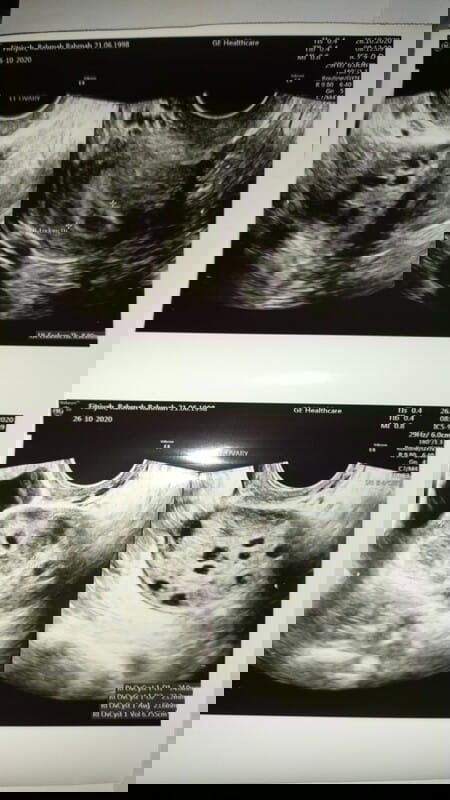

Merencanakan Kehamilan

sel telur kecil²

Assalamualaikum bunda2 disini ada gk bunda yg dulu sel telurnya kecil2? sekarang saya lagi ngalamin hal ini😟2 bln terakhir dikasih obat sama dokter gk ada perubahan,jdi strategi selanjutnya harus suntik hormon diperut setiap hari sampai sel telurnya membesar. utk saat ini saya takut jd saya butuh waktu😔pdhl udah pengen banget punya anak, sdh 5 thn pernikahan😔 krna berhubung sya overweight, jdi harus nurunin BB jaga makan n sering olahraga juga. apakah ada strategi lain buat naikin ukuran sel telur bun? Makasih atas semua jwban bunda2 disini, maaf gabisa bls satu2, semoga yg lagi hamil diberikan kesehatan&keselamatan sampai lahiran🙏🤗💛